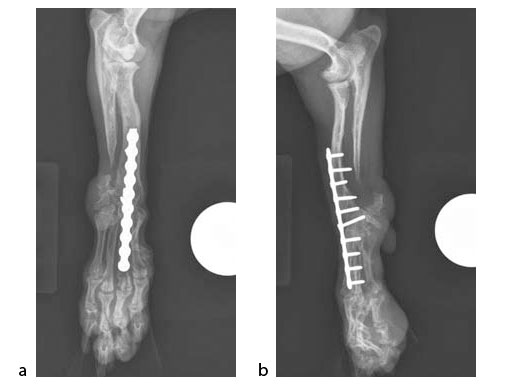

A 5-year-old female 3.5 kg dachshund with bilateral carpal hyperextension secondary to erosive polyarthroplathy (rheumatoid arthritis) (Fig 3, Fig 4) was treated bilaterally with a staged pancarpal arthrodesis with straight LCPs. The right carpus was operated first and healed in 10 weeks. The left carpus was operated 5 months after the initial surgery (Fig 5). Complete healing was noted 3 months postoperatively (Fig 6).

At the most recent follow-up 20 months postoperatively (first arthrodesis), the dog was comfortable and very active. The plates were selected based on the small bone size and the risk of secondary osteopenia. Locking screws are important to prevent screw loosening in patients with poor bone quality, especially in the case of pancarpal arthrodesis where high bending forces must be neutralized.